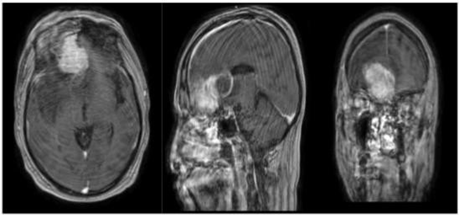

Magnetic resonance imaging (MRI) allowed us to make the diagnosis of an esthesioneuroblastoma (Figure 2).

Figure 2 Brain MRI with contrast injection confirming tumor with perilesional edema.